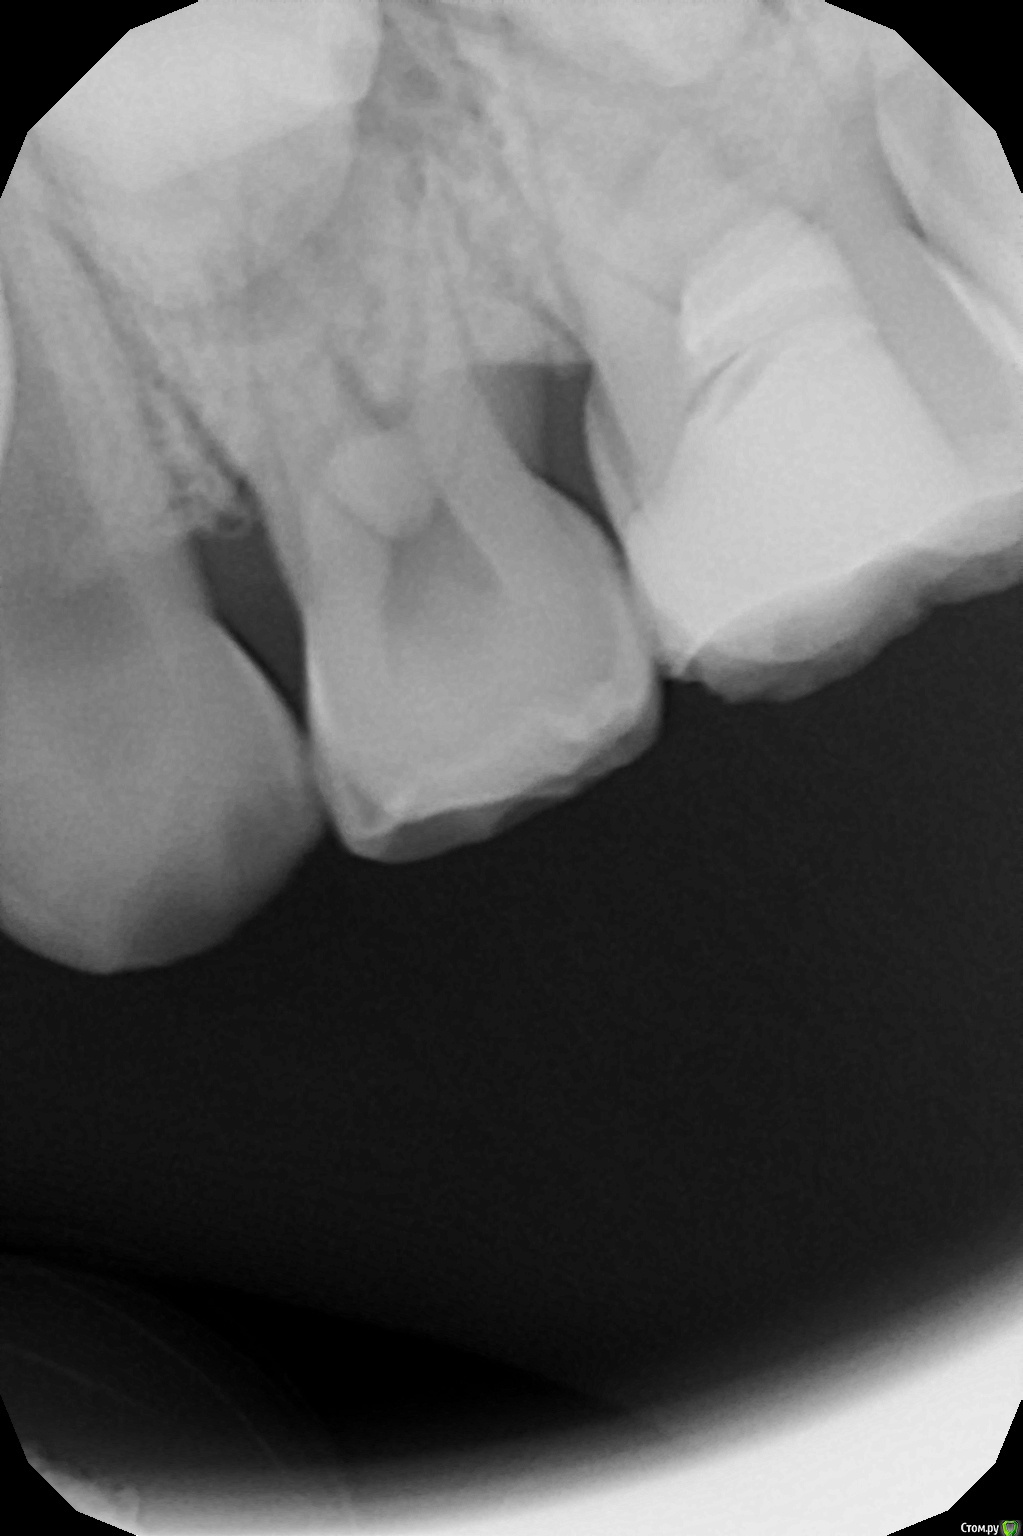

crown Опубликовано 19 октября, 2016 Автор Поделиться Опубликовано 19 октября, 2016 8 лет 2 месяца назад лечил 6.5 пульпитный с триоксидентом, сегодня отек в районе четверки и перкуссия ее болезненна, но она интактная. Решил полезть в 6.5, мб2 и мб1 прошел, закинул кальций, в небный не могу войти орет, дистальный вообще туго, облитерировалось по ходу все к чертям, пока оставил так. Но меня терзают сомнения, так как симптоматика вся на четвертом зубе и на снимке изменения в 6.4. Мамаша еще мозг выносит, сыпит вопросами как из пушки и тут не понятно то ли ребенка лечить то ли ей на вопросы отвечать. Ссылка на комментарий

Mikhail_29_rus Опубликовано 23 октября, 2016 Поделиться Опубликовано 23 октября, 2016 8 лет 2 месяца назад лечил 6.5 пульпитный с триоксидентом, сегодня отек в районе четверки и перкуссия ее болезненна, но она интактная. Решил полезть в 6.5, мб2 и мб1 прошел, закинул кальций, в небный не могу войти орет, дистальный вообще туго, облитерировалось по ходу все к чертям, пока оставил так. Но меня терзают сомнения, так как симптоматика вся на четвертом зубе и на снимке изменения в 6.4. Мамаша еще мозг выносит, сыпит вопросами как из пушки и тут не понятно то ли ребенка лечить то ли ей на вопросы отвечать.У меня тоже бывали подобные случаи, но как правило, зуб выстреливал сразу после лечения. Но тогда я "грешил " с гемостазом. На 65 зубе правило "3 минут" сработало? Гемостазу не помогали ? Если все с 65 сделали верно , то скорее всего 64. В любом случае, удачи в решении не самой простой задачи в особенности с непростой мамой Ссылка на комментарий

crown Опубликовано 23 октября, 2016 Автор Поделиться Опубликовано 23 октября, 2016 На счет гемостаза не помню. Мож терпел малец и не жаловался, пока щека не припухла. Спасибо Михаил. Ссылка на комментарий